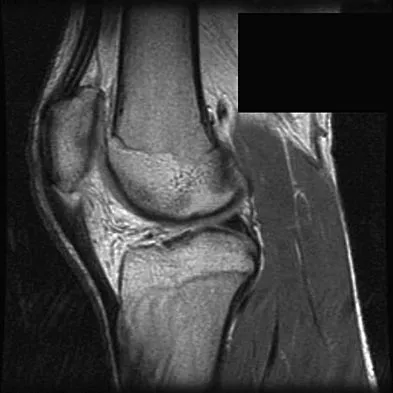

A 24-year-old athlete has a painful right shoulder. Figure 30 shows an intra-articular photograph that was obtained through a posterior portal during arthroscopy; the labrum is indicated by the arrow. Based on these findings, management should consist of

Explanation